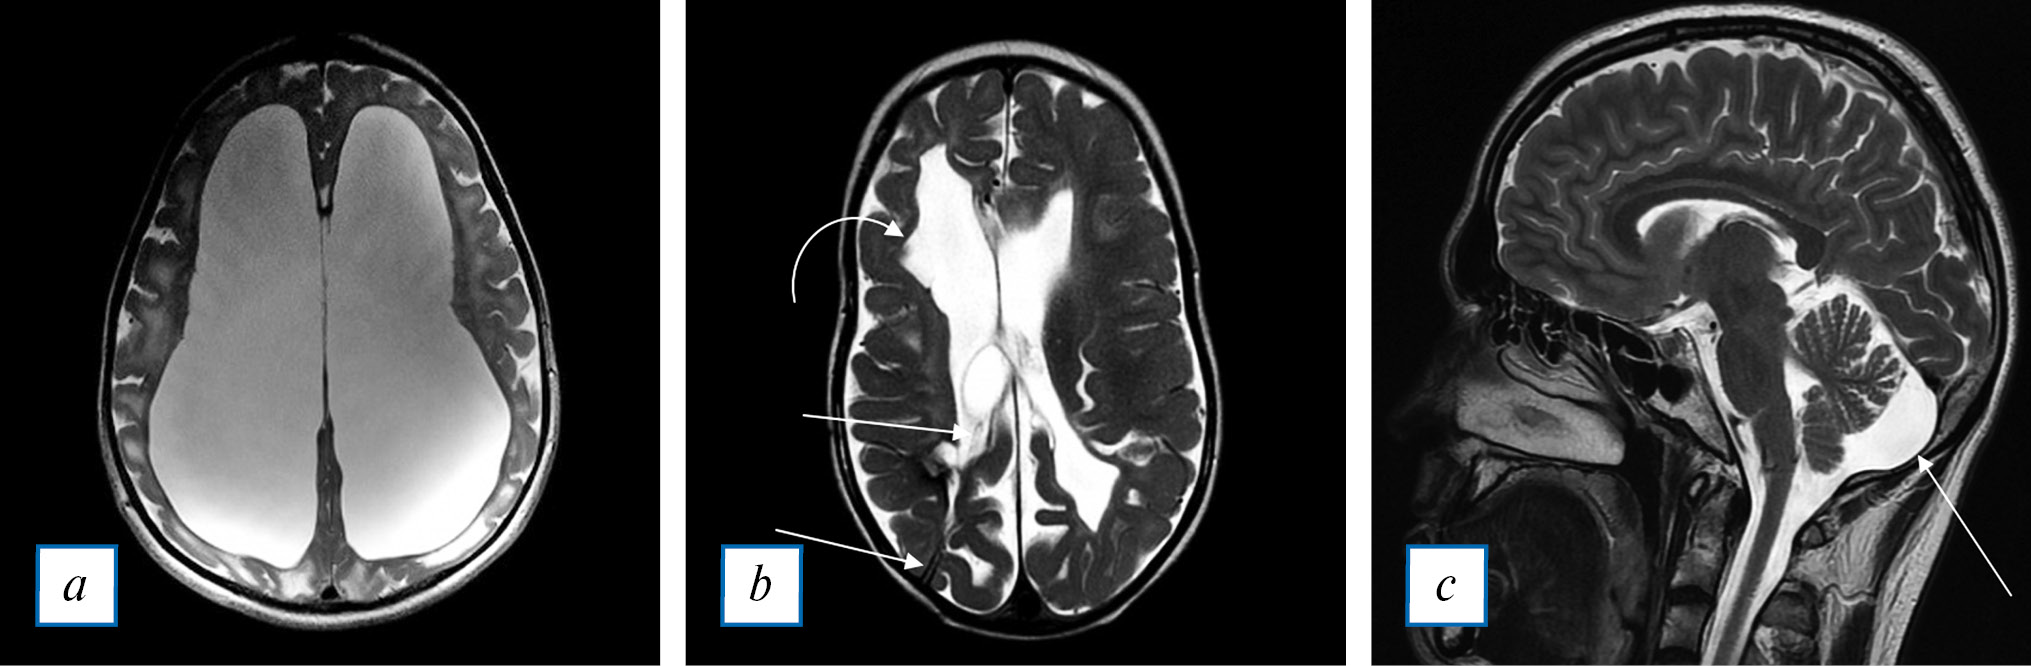

Расширенные ПВП не являются специфической находкой при МПС, т.к. встречаются и при других заболеваниях сосудистой, воспалительной, инфекционной и опухолевой природы, а также в норме. Расширения ПВП чаще всего располагаются пе-ривентрикулярно и в базальных ганглиях, однако описаны случаи локализации в стволе мозга и мозжечке [16]. Обычно диаметр ПВП варьирует от 2 до 8 мм (рис. 1, а), однако в ряде публикаций описаны и более крупные (гигантские) размеры (рис. 1, б) [8, 15, 17].

Рис. 1. МРТ головного мозга, Т2-ВИ в аксиальной плоскости: а, б — стрелками показаны множественные расширенные периваскулярные пространства; отмечается также расширение субарахноидальных пространств и борозд мозга, что свидетельствует об атрофии. Кости черепа утолщены.

Fig. 1. Head MRI, T2 WI axial plane: a, б — arrow: multiple enlarged perivascular spaces; subarachnoid space and cerebral sulci are also dilated, that indicates cerebral atrophy. Skull bones are thickened.